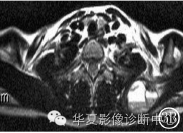

MR片(图3A~3C)示:左侧肩胛骨区呈膨胀性不规则的混杂信号,T1呈低信号,低层局部见略高信号,T2呈高信号,低层呈相对低信号,可见“液‐液”平面;肿块边界清楚,其内可见长T1、短T2的分隔,增强扫描病灶内分隔明显强化。

图3A MRIT1WI:左肩胛骨呈低信号影,液‐液平面不明显 图3B MRIT2WI:左肩胛骨病灶呈明显液‐液平面,上层高信号,下层低信号,其内见分隔 图3C MRI增强扫描:左肩胛骨病灶分隔明显强化